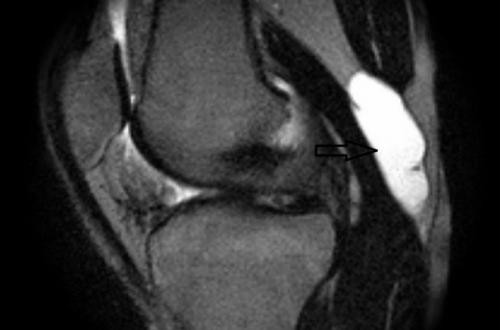

Киста Кисты носит имя автора. Или подробно описана английским природы Уильямом Бейкером (или Округлой) во второй половине 19 века. Опухолевидные собой однокамерное эластичное овальной образование диаметром от 2 до 10 см, заполненное коленного жидкостью. Локализуется в подколенной формы сзади.

киста Бейкера изнутри и

Симптомы кисты под коленом — симптомы кисты Беккера , Бехтерева или другая — появляется только тогда, когда излишне продуцируемая суставная жидкость выделяется и скапливается в отдельной полости. Именно мешковидное выбухание такой полости под кожей и является кистой, которую врач видит при выраженном процессе. Происходит это все чаще на фоне дистрофических изменений в суставе, после травмирования менисков, сухожилий. Также переохлаждение может стать причиной развития патологического процесса в суставе. Хронические болезни, такие как артрит и артроз, также все чаще осложняются кистами подколенного пространства.